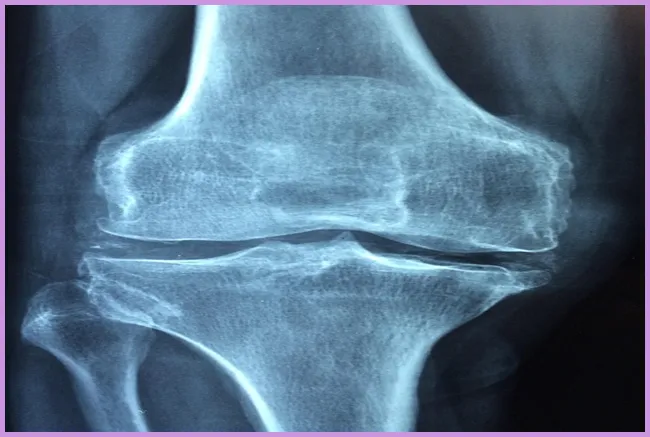

관절염은 매우 일반적인 질환으로, 관절의 염증으로 인해 발생하는 여러 증상을 포함합니다. 관절염의 종류는 다양하고, 그중에서도 퇴행성 관절염과 류머티즘성 관절염이 가장 흔합니다. 이들 두 가지는 어깨 통증의 주요 원인이 될 수 있습니다. 관절염에 걸리면 관절이 붓고 아프며 운동이 제한될 수 있습니다.

어깨 통증이 지속되면 어떤 검사를 받아야 하나요?

어깨 통증이 3주 이상 지속될 경우, 정형외과 전문의를 방문하여 엑스레이, MRI 또는 초음파 검사를 통해 정확한 진단을 받는 것이 중요합니다. 이를 통해 통증의 원인을 파악하고 적절한 치료 계획을 세울 수 있습니다.